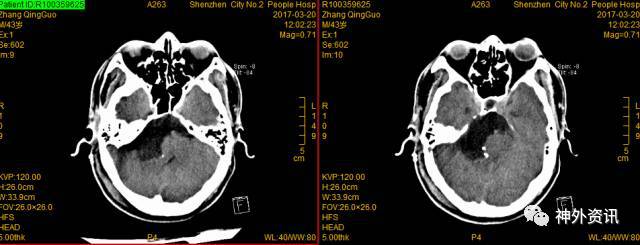

4. 术前影像学检查如下:

右桥小脑角区可见不规则形异常信号肿块,边界清晰,密度尚均匀,范围约6.8*5.9*5.8cm,病灶沿间隙匍匐生长,呈长T1长T2信号改变,DWI呈高信号,增强扫描未见明显强化,与周围组织分界清,基底动脉受压向左侧移位,中脑导水管,脑干、小脑、第四脑室受压变窄,第三脑室、双侧侧脑室扩张积液导。

术后72小时CT

术后14天复查CT